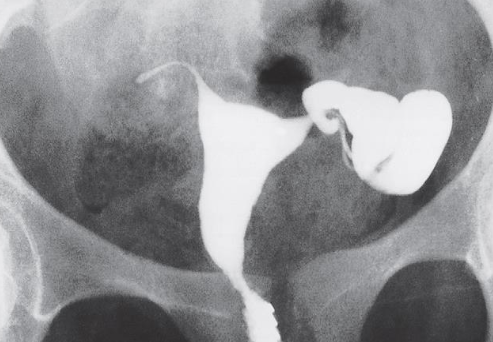

FEMALE REPRODUCTIVE SYSTEM IMAGING # Y

HSG – Unilateral Hydrosalpinx

HSG – Bilateral Hydrosalpinx

Calcified Uterine Leiomyoma

Plain radiograph:

- Calcification in a large uterine fibroid